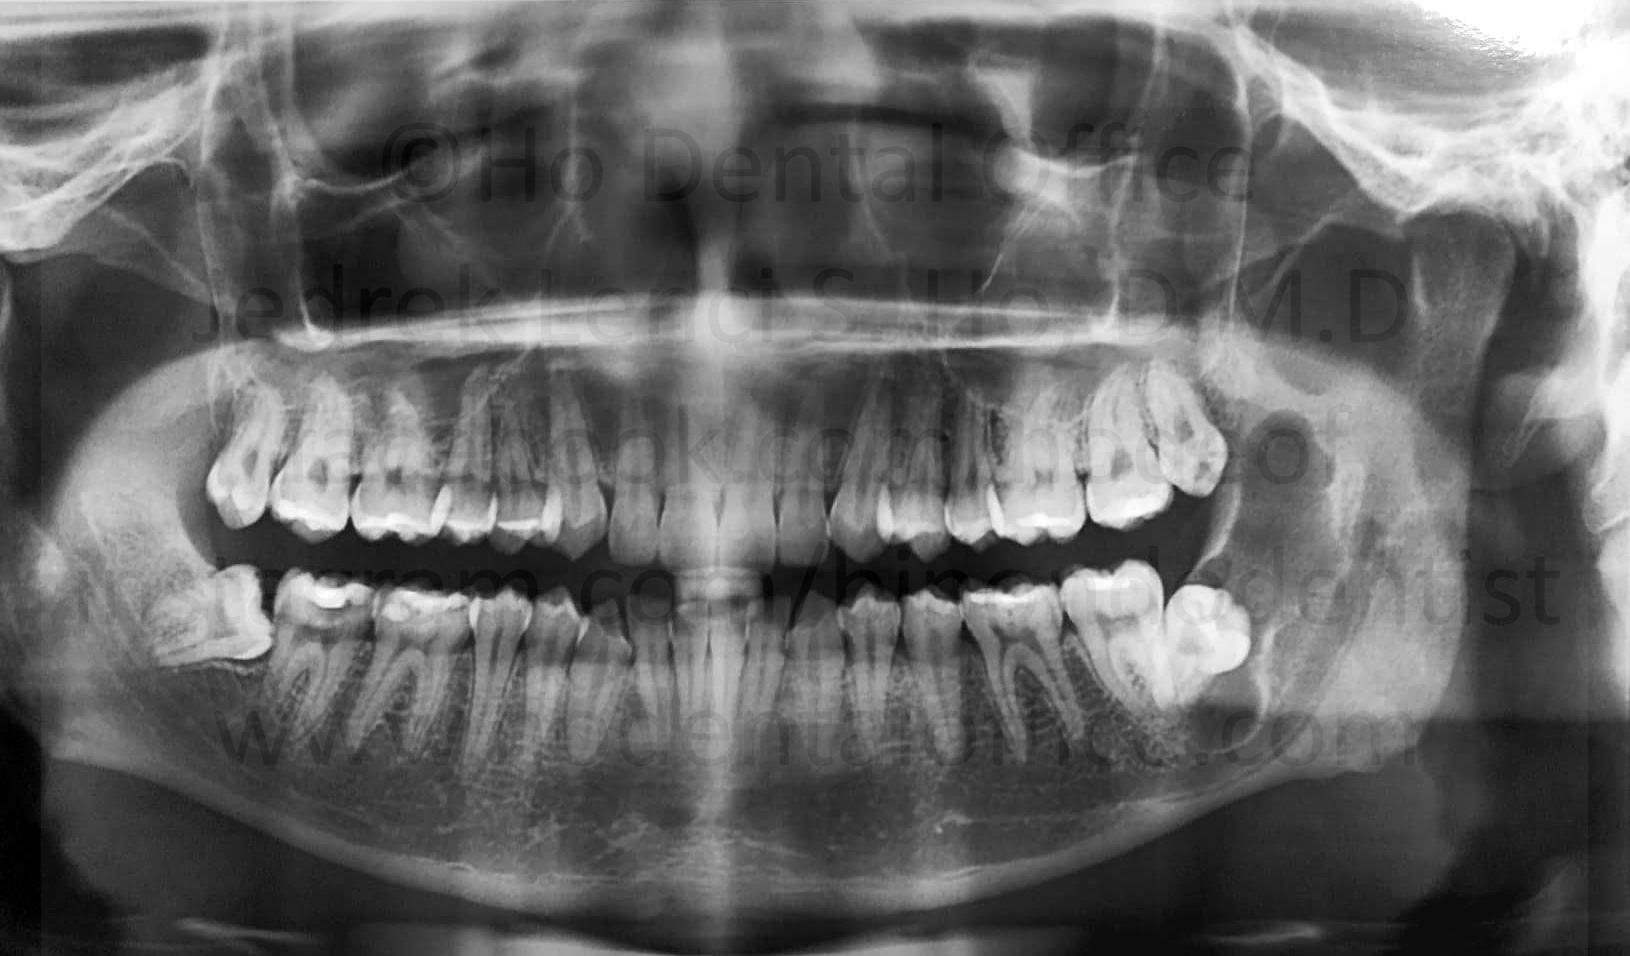

prevention of tooth decay - Food impaction is relatively common on exposed partially impacted tooth, and may damage the neighboring tooth because of cleaning difficulties.

![]() | ![]() |

| tooth decay on the lower second molar, beside the impacted wisdom tooth | |